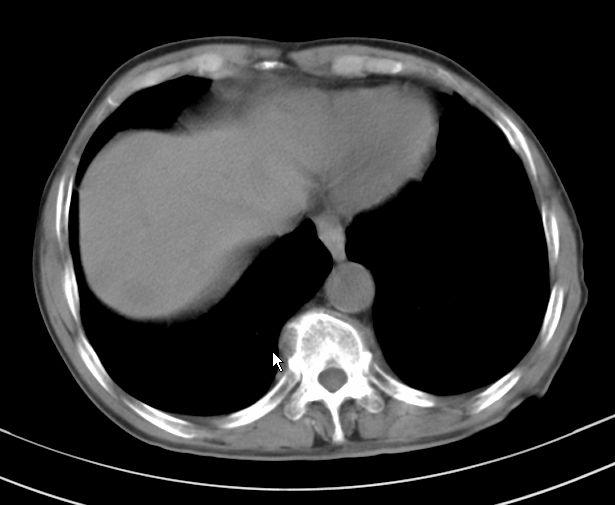

楼主说是炎症,凭啥?典型的周围型肺癌(腺癌可能性大),肝内可能已有转移,强化看看吧。